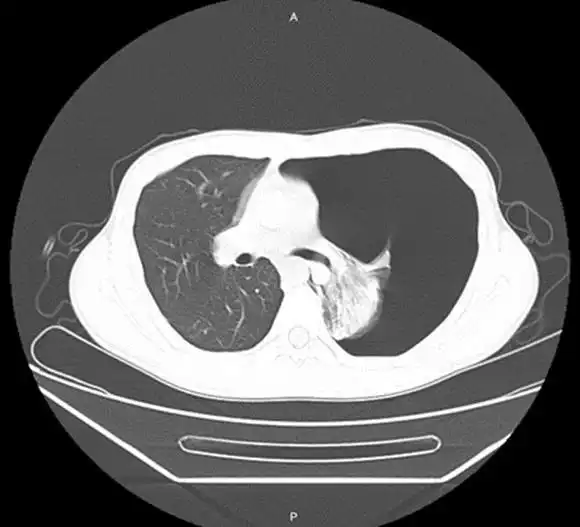

X-quang ngực và cắt lớp vi tính (CLVT) tại thời điểm nhập viện: Ghi nhận hình ảnh tràn khí màng phổi trái lượng nhiều, gây xẹp nhu mô phổi trái và đẩy lệch trung thất sang bên đối diện.

| Hình ảnh: Xquang, CLVT lúc vào viện: Hình ảnh tràn khí màng phổi số lượng lớn gây đè ép nhu mô phổi trái và trung thất. | |